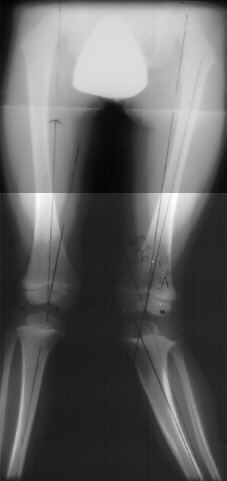

At this time the child was experiencing significant pain and inability to ambulate. He was treated with varus producing closing wedge osteotomy of the proximal tibia with neutral alignment

X-Ray Set 3. Post-Op, Neutral alignment